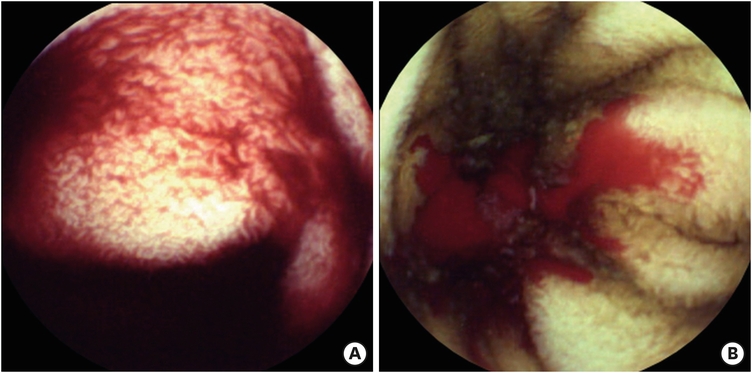

Exploratory laparotomy with intraoperative push-endoscopic bleeding control revealed multiple adhesive bands on the small bowel, and adhesiolysis was performed. Vascular anomalies such as angiodysplasia or hemangioma were not found in the mesentery including the serosa side of the bowel. After inspection of the intra-abdominal cavity, the gastroenterologist examined the whole small bowel by oral intubation with colonoscope (EVIS EXERA II® CF-Q180AL, working length 1,680mm; Olympus America, Center Valley, PA, USA). While the gastroenterologist inspected the small bowel mucosa, the surgeon performed gentle manual milking of the small bowel down to the ileocecal valve. Multiple mucosal bleeding foci were found from the proximal jejunum to the proximal ileum. There were no visible blood clots suspicious of bleeding at the opening site of jejunojejunostomy. Hemo-clippings were applied in 10 places, and argon plasma coagulations (APCs) were performed 34 times (Fig. 2).

Fig. 2

Intraoperative endoscopy. Multiple bleeding foci were treated with (A) argon plasma coagulations and (B) hemo-clippings.